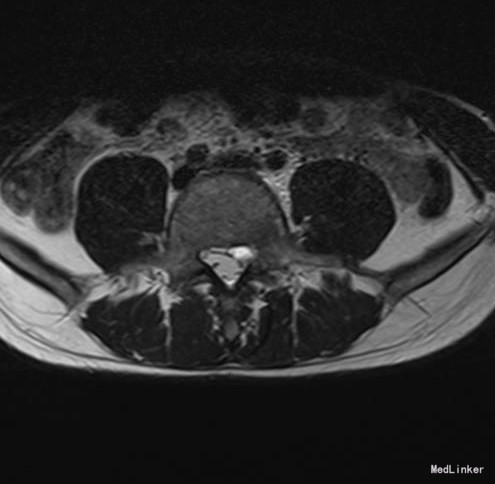

椎管侧隐窝占位1例

左侧下肢放射痛1月加重2天

腰椎前屈受限,腰4-5左侧棘突旁压痛,左侧直腿抬高试验小于30°,肌力正常。

腰椎椎管内占位 腰椎后路开窗减压+椎间融合+内固定术